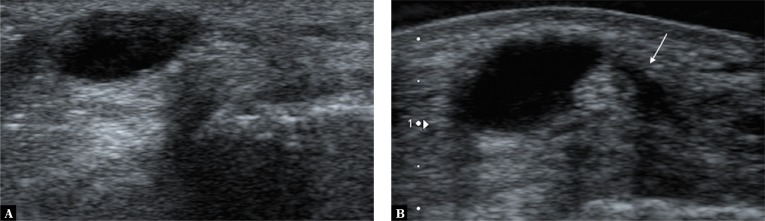

The first step of the differential workup involves identifying the structure’s location as for cartilage superficial to the bone contour or fluid layer situated in a synovial recess, bursa or sheath. Anechoic focus seen at site of injury may be consistent with a fluid-filled structure of various types, as well as a whole range of degenerative foci. A simple compression test helps to further distinguish between fluid-filled structures and other lesions. When pressure is applied with the transducer, fluid-filled structures change shape, with the fluid sometimes changing location or entirely disappearing from view. The test, however, may come out negative, if the fluid collection has high pressure, and the change of shape may only be very slight. To differentiate a structure filled with high-pressure fluid from other lesions the Doppler option may be used, as it shows fluid fluctuation. The fluid-filled area will fill with color, Doppler signal (image of fluid movement), especially while pressure is being released (Fig. 13).

Fig. 13.

Additional symptom facilitating differentiation of fluid-filled structures in equivocal findings: A. a typical fluid-filled structure in the popliteal fossa, consistent with an enlarged synovial bursa of the gastrocnemius muscle; B. the fluctuation symptom showed by the power Doppler option, visible as colour filled the fluid space due to the fluid motion caused by the pressure applied with the transducer